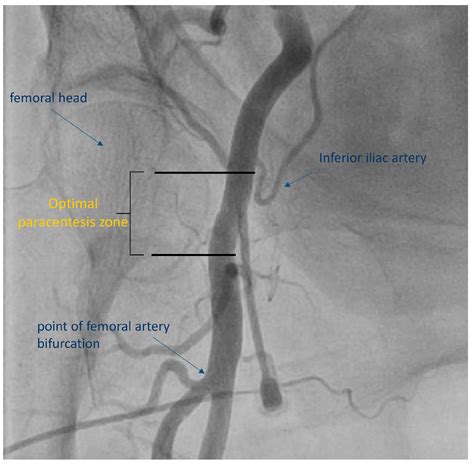

By far, the most frequent utilization of the Sfa medical abbreviation in surgical and vascular contexts is in reference to the Superficial Femoral Artery. This artery is a major vessel located in the thigh, acting as the primary source of blood flow to the lower extremity. In vascular surgery, clinical notes often track the patency of this vessel, especially in patients suffering from Peripheral Artery Disease (PAD).

When physicians document an SFA blockage or stenosis, they are signaling a significant condition that may require intervention, such as angioplasty or stenting. Because the SFA is prone to atherosclerosis, identifying this vessel in medical records is a daily task for vascular surgeons, interventional radiologists, and vascular sonographers.